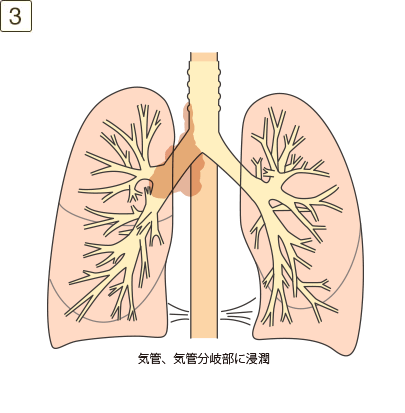

充実成分径>7cm、または大きさを問わず横隔膜、縦隔、心臓、大血管、気管、反回神経、食道、椎体、気管分岐部への浸潤、あるいは同側の異なった肺葉内の副腫瘍結節